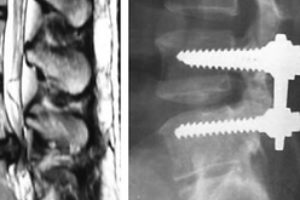

A unique method of spinal surgery successfully implemented in clinics of Israel. Medical staff hospital Meir became parties to the implementation of the patent for the Titanium implants Chip. …